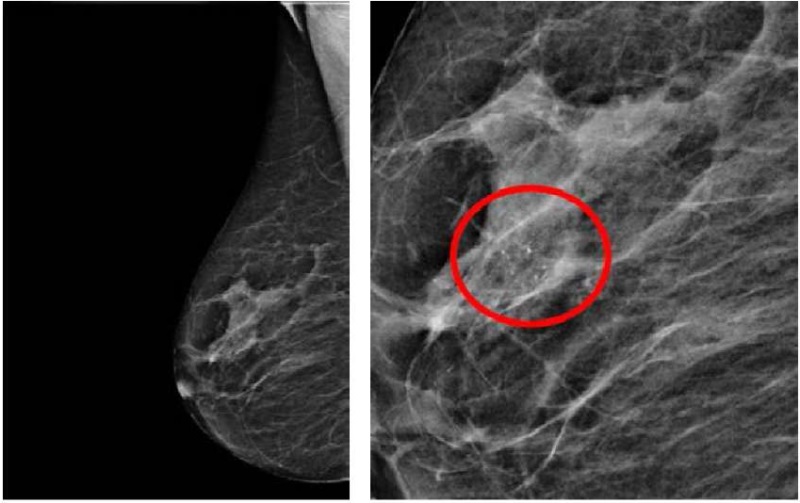

Диагностика РМЖ 0 стадии включала клиническое обследование, ультразвуковое исследование молочных желез и регионарных зон, маммографию (рис. 1), томосинтез. Для исключения мультицентричности процесса МРТ (магнитно-резонансная томография) молочных желез с контрастом, для верификации процесса применяют трепанобиопсию для гистологического исследования и определение чувствительности к рецепторам эстрогена и прогестерона.

Рисунок 1. Маммография (справа — зона кальцинатов)

Figure 1. Mammography (on the right — area of calcifications)

Размер поражения в молочной железе DCIS и LCIS составил от 2 до 60 мм по данным маммографии и МРТ молочных желез. Данные размеры обусловлены в основном зоной микрокальцинатов в молочной железе.